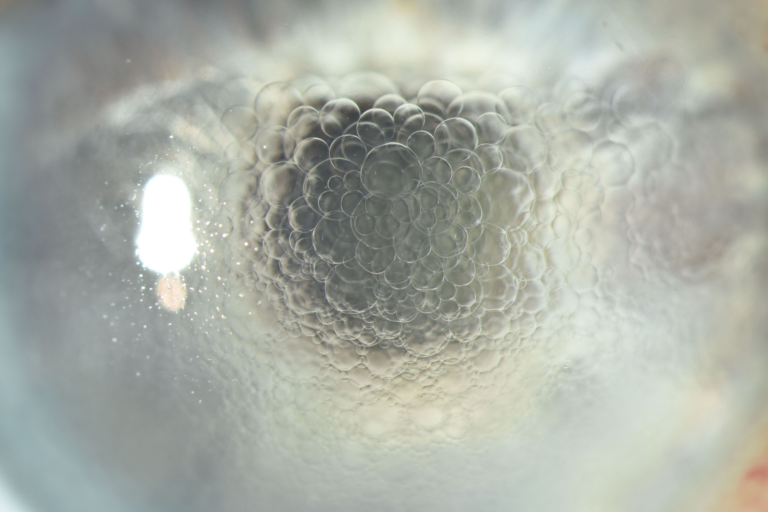

Third place - Beathan Halbert-Fettes, Ophthalmic Photographer, South Tyneside and Sunderland NHS Foundation Trust

Finally, Beathan Halbert-Fettes took third place with an crystal clear image of a corneal laceration.

Rosalyn Painter, Ophthalmic Healthcare Science Education Manager at GREG, said of the 3rd place winner, “Beathan’s image shows skill and dexterity; the illumination and focus perfectly illustrate the lesion”.